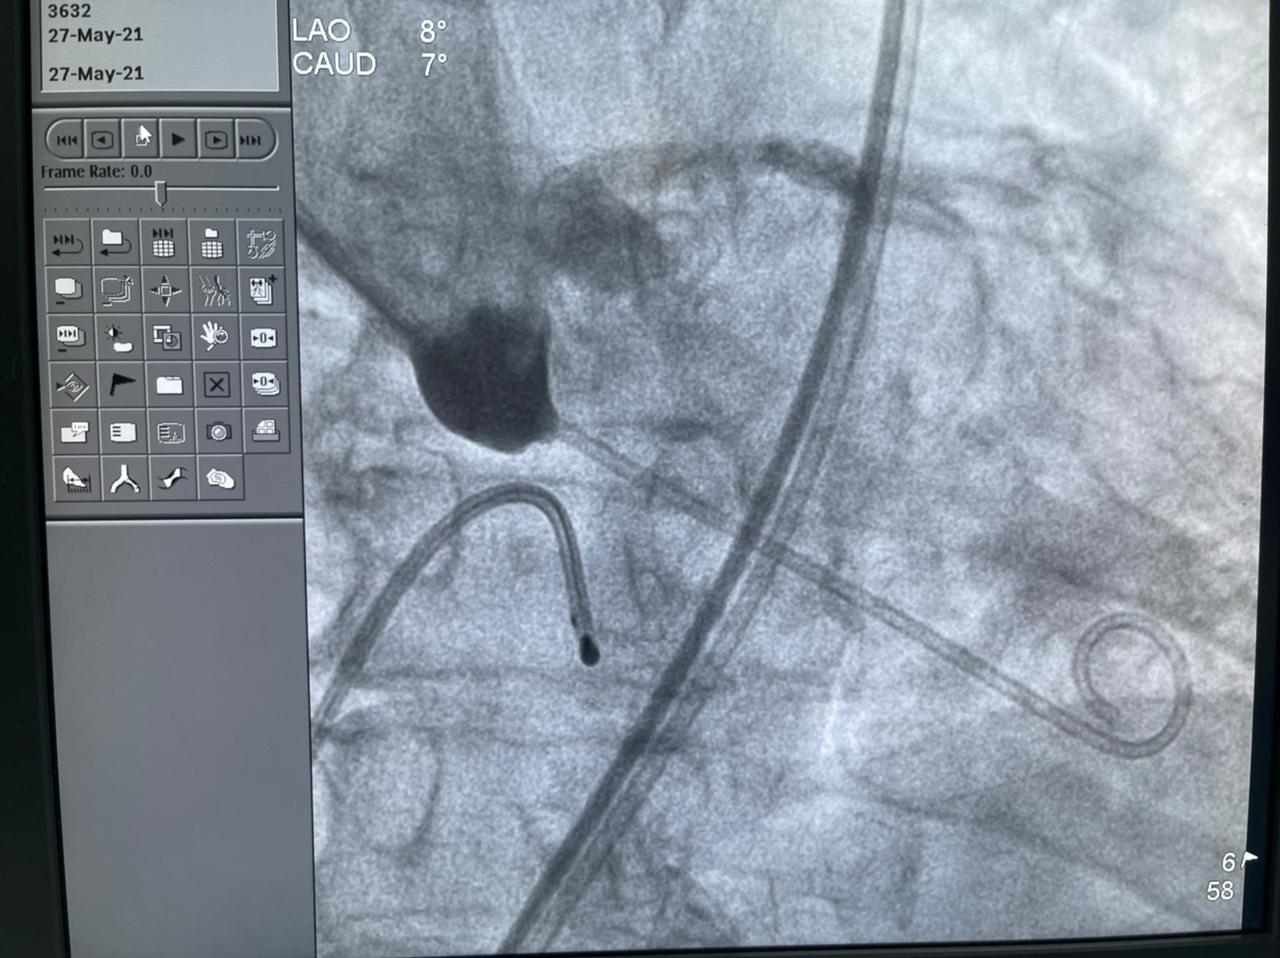

وأضافت الهيئة أن الحالة الثانية هي عملية زراعة الصمام الأورطي لمسنة تبلغ من العمر 78 عامًا، كانت تعاني من ضيق شديد بالصمام الأورطي، وتمت العملية بنجاح بعد أن كانت تعاني من تعب شديد وضيق بالتنفس وآلام بالصدر ونوبات إغماء، وتم إقرار علاج المريضة بعملية زراعة الصمام نظرًا لتقدم عمرها والضعف العام لحالتها الصحية، وتم إجراء العملية بتقنية التافي العالمية التي يتم بها تغيير الصمام الأورطي عن طريق القسطرة.

واستكملت أن الحالة الثالثة لمريضة تبلغ من العمر 70 عامًا، تعاني من قصور شديد بالشرايين التاجية للقلب وانسداد تام مزمن بالشريان التاجي الأيمن، إضافة إلى انسداد مزمن بالشريان التاجي الدائري الملنف وضيق شديد بالشريان الأمامي، ولها بنت مريضة من ذوي القدرات الخاصة، ولا تستطيع التغيب عنها لفترة طويلة، فتم علاجها على وجه السرعة عن طريق توسيع للشرايين بالبالونات العادية والدوائية إلى جانب تركيب دعامات دوائية لها باستخدام أحدث التقنيات العالمية بنجاح، واستطاعت الخروج من المستشفى في أقل من 24 ساعة لتعود إلى بيتها وابنتها التي تحتاج إلى رعايتها.

وتابعت الهيئة أنه قام بإجراء العمليات للمرضى الثلاثة في يوم واحد، فريق من أمهر الأطباء الأخصائيين والاستشاريين في علاج أمراض القلب والقساطر القلبية، يضم، الدكتور طارق رشيد أستاذ القلب والقسطرة وخبير حالات الانسداد المزمن للشرايين التاجية ورئيس قسم القسطرة القلبية بمستشفى النصر التخصصي، والدكتور ياسر صادق استشاري القلب وخبير القسطرة القلبية، الدكتور أمير البسطويسي استشاري جراحة القلب والصدر، الدكتور أحمد شبل استشاري القلب والقساطر التداخلية، الدكتور محمد علم الدين استشاري القلب والقسطرة العلاجية، الدكتور محمد لبيب استشاري جراحة الأوعية الدموية، وإخصائي علاج أمراض القلب والأوعية الدموية الدكتور معتز سلامة و الدكتور محمد عطا، أخصائي علاج أمراض القلب والقسطرة العلاجية الدكتور مصطفى رفعت، الدكتور أحمد عبد الرؤوف أخصائي التخدير بالمستشفى.